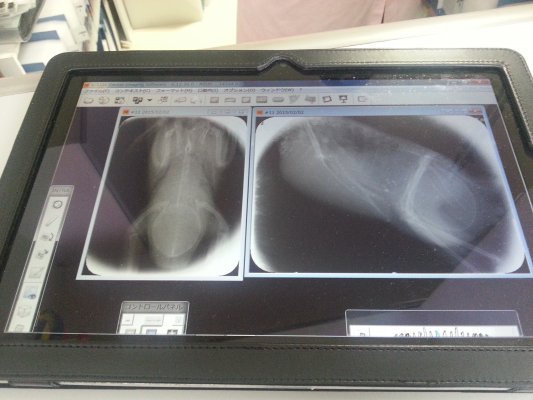

以下の書き込みの心配点ですが、この図が、なにかヒントになりそうだなと思ったので、写真にとってアップしてみますね(スキャナじゃなくで見づらくてすみません)以前に趣味で獣医さんの本を紀伊国屋書店でかいました。その本に、ハトの消化器と、雌鳥の生殖管と、雄鳥の泌尿生殖器系の図が乗っていました。

子宮で育った卵がでる管が、糞の出るお尻のアナに途中でくっついている構造みたいなので、糞が出ていても卵詰まりは起きそうだな〜と思ったので図を紹介してみました。腎臓から伸びる尿の管が子宮に圧迫されて、おしっこが出ないから尻がプニプニなのかな?とも思いました。獣医ではないので、不確かな発言で申し訳ないのですが。

図がお役にたてば幸いです。

わかりやすい写真ありがとうございますっ!

写真のまんまでしたっ!まさにその写真通りでしたっ!

お尻が、ぷにぷにしていたのは尿が溜まっていたようで

卵の硬さが確認できない状態なので、

レントゲンで卵を確認してから

尿を抜いてから指圧でお腹を触ると

なんらかの要因で軟卵になってしまったようで、、